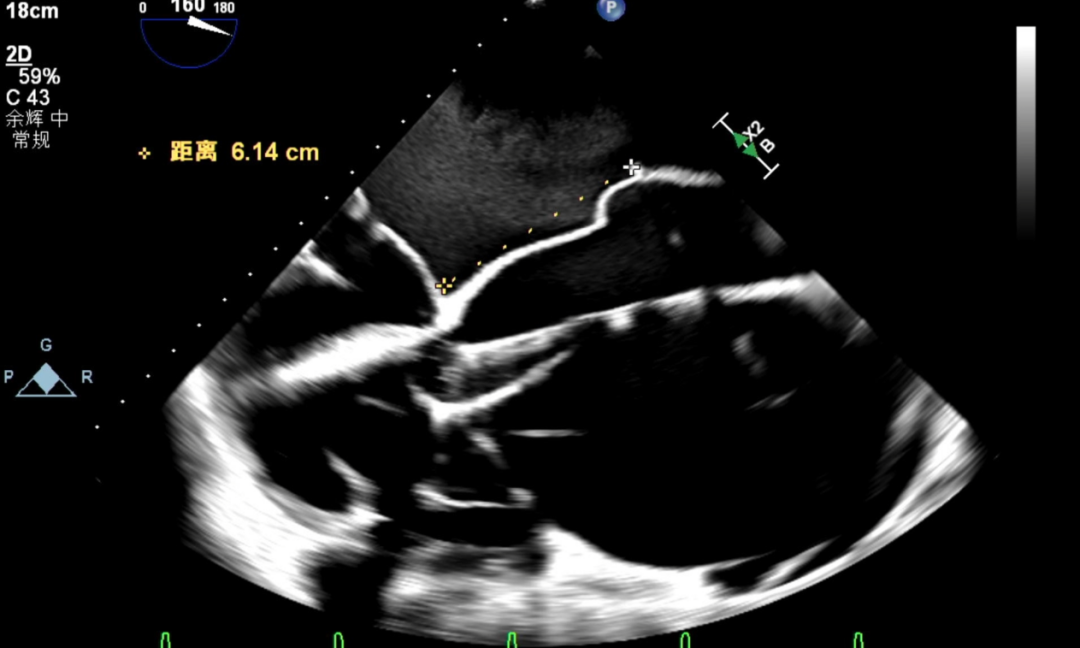

患者在全麻状态下,经超声引导建立右侧股静脉入路,送入房间隔穿刺系统。于上下腔连线中部偏下、主动脉短轴切面中部略偏后位置尝试穿刺,多次推送穿刺针均见帐篷样隆起,但穿刺点高度均偏高,调整穿刺针位置后仍未能获得合适的房间隔穿刺高度。遂决定先于较高位置行房间隔穿刺,首次穿刺高度为6.14cm,将房间隔导丝送至左上肺静脉作为定位参照。更换房间隔穿刺系统后再次尝试穿刺,仍难以达到理想高度。

首次房穿高度

怎么上穿刺鞘攻克巨大左房伴转位穿刺难关!温医大附一院周浩教授团队创新应用“导丝定位+可调弯鞘”技术完成高难度TEER手术_https://www.jmylbn.com_新闻资讯_第14张

房间隔导丝送至左上肺静脉作为定位参照